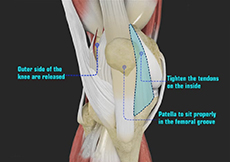

Patella Stabilization

Patellar (kneecap) instability results from one or more dislocations or partial dislocations (subluxations).

Patellafemoral Realignment